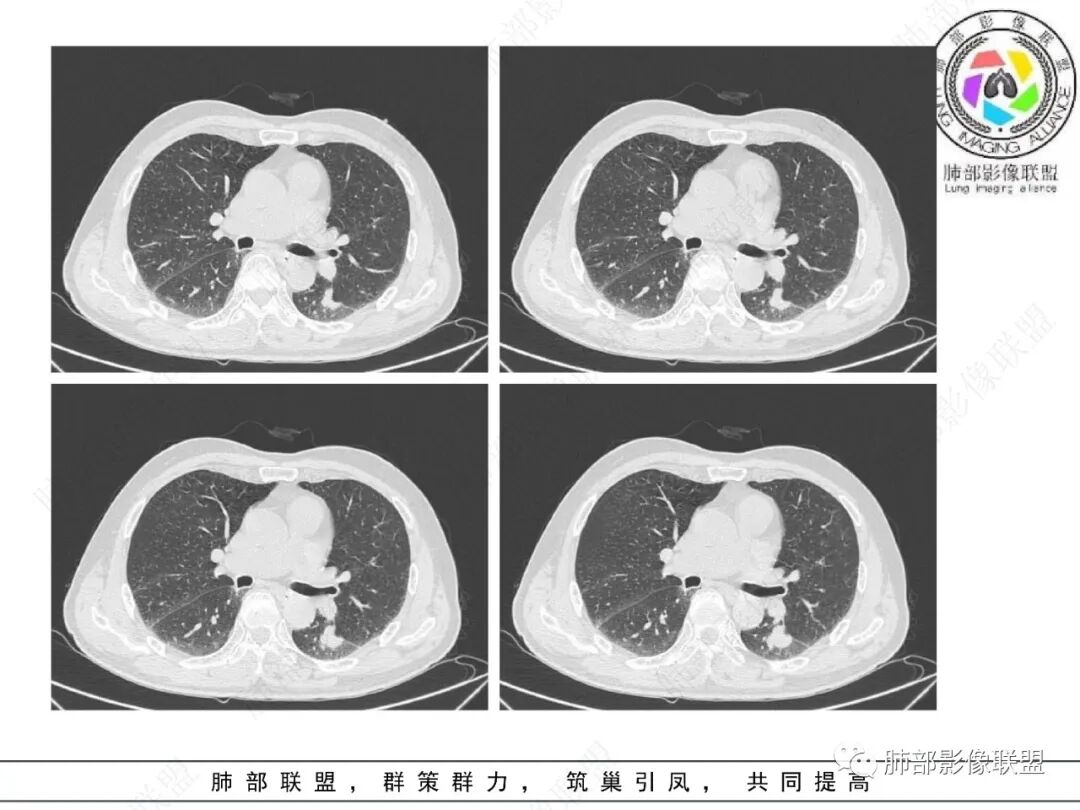

影像学表现:左肺下叶背段近叶间裂旁不规则实性密度结节影,图像未明确显示与支气管关系。边界清,整体膨隆感较明显,边缘显示分叶,偶见段毛刺,叶间胸膜“L”形牵拉凹陷,密度均匀,未见空洞或液化,也未见明显脂肪密度及钙化,轻到中度渐进性强化,未见明确蛇纹状血管应。左肺门可见多发小淋巴结影,纵隔内未见明显肿大淋巴结影。

未见明确卫星灶。

小结:老年吸烟男性,较大孤立结节影,应高度警惕新生物。病灶强化,分叶,收缩力强,应当怀疑恶性,尤其是常见的肺腺癌。尽管“大细胞癌”的病理意见出乎预料。